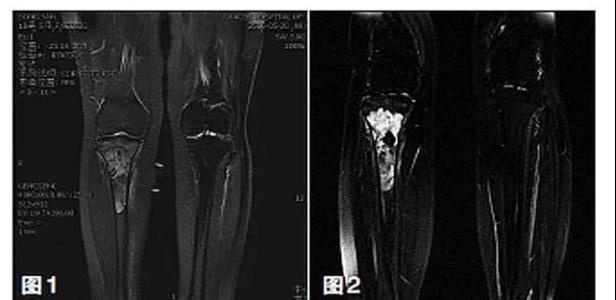

保肢治療指經(jīng)典型骨肉瘤在多學(xué)科團(tuán)隊(duì)醫(yī)生共同努力下完成的新輔助化療、保肢手術(shù)和輔助化療等一系列治療總稱,其目的是在提高患者生存率的前提下,減少局部復(fù)發(fā)、盡量保留良好的肢體功能。肢體經(jīng)典型骨肉瘤保肢治療方法如下圖所示: